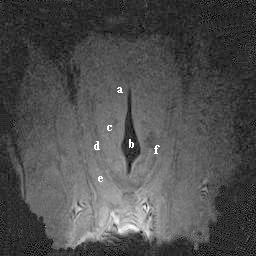

| dc.description.abstract | A study was performed to establish the appearance of normal equine laryngeal cartilages using magnetic resonance imaging. Specimens were acquired from clinically normal horses that were euthanized for reasons other than respiratory disease. Three in situ and 5 ex vivo larynges were imaged using a 0.3 Tesla system. Images were obtained in the transverse plane using T1-weighted 3D spin echo, T2-weighted 3D spin echo, T2-weighted gradient echo, short tau inversion recovery (STIR), and proton density spin echo sequences. Five ex vivo larynges were also imaged in the transverse plane using a 1.5 Tesla system, sequences included T1-weighted 3D spin echo, T2-weighted 3D turbo-spin echo, turbo inversion recovery (TIRM), and proton density spin echo sequences. A frozen gross laryngeal specimen was sliced in 5-mm transverse sections for comparison to the MR images. Excellent correlation was found between MR images and the gross transverse sections. Successful imaging was accomplished using both imaging systems; however, the 1.5 Tesla system yielded superior image resolution. The 0.3 Tesla imaging system would accommodate the intact equine head, which was not possible using the 1.5 Tesla MRI system. The internal morphology of the laryngeal cartilages was clearly identified in all imaging sequences obtained. Cartilages were found to differ in signal intensity based on the tissue composition and imaging sequences performed. MRI was determined to be a useful imaging modality for evaluating the cartilage morphology of the equine larynx. Further investigation is required to document pathologic morphology. | en |